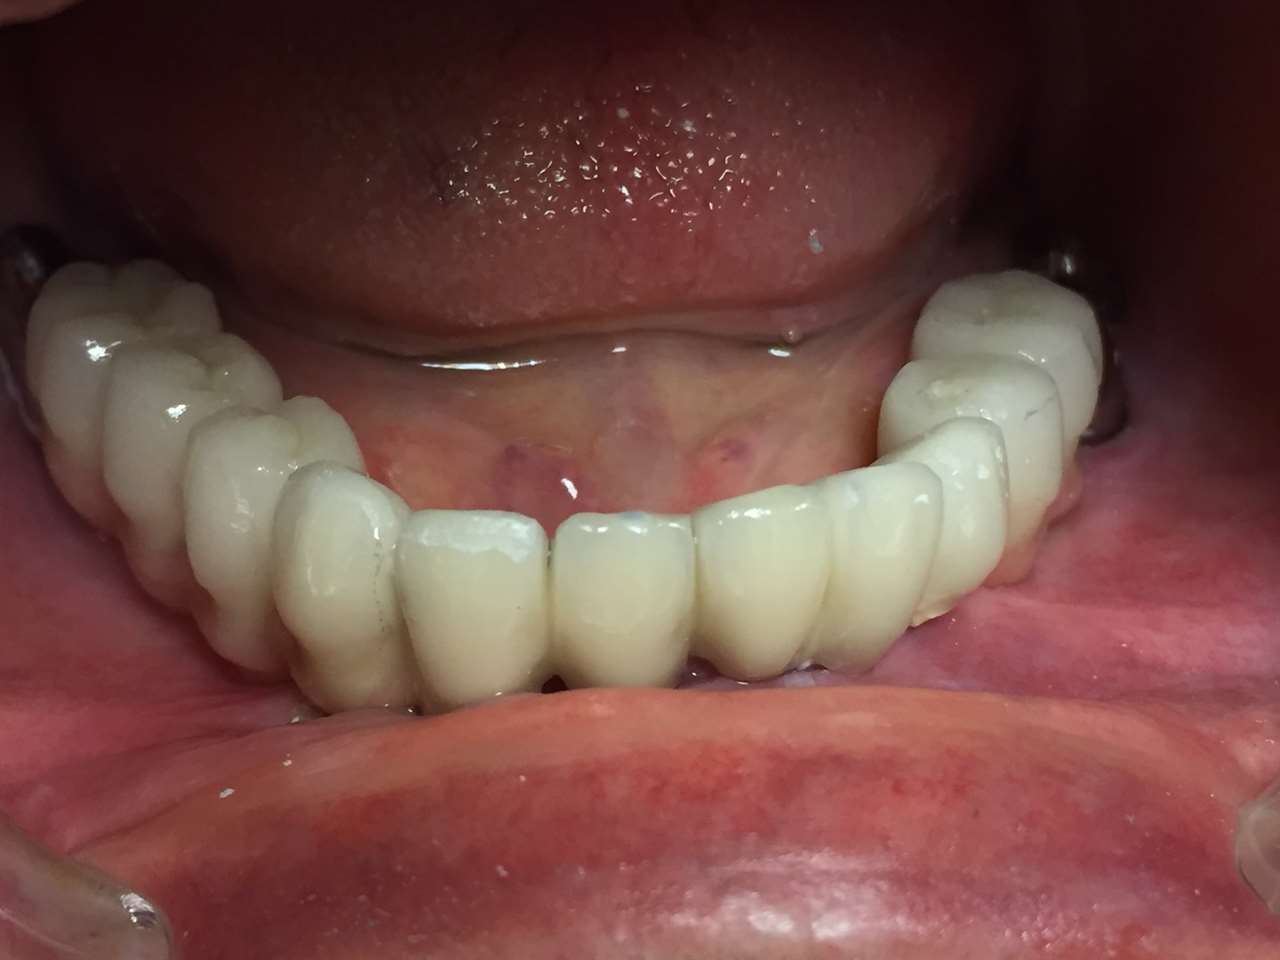

Teljes alsó,felső állcsont helyreállítása azonnal

terhelhető implantátumokkal és porcelán hidakkal.